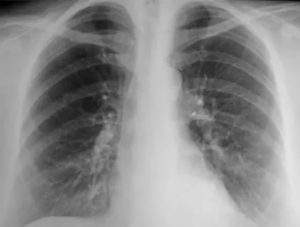

Обнаружить кальцинаты в определенном органе возможно при использовании рентгенографии.

Снимок предоставляет возможность обнаружить не только отложения кальциевых солей, но также и прочие нарушения здоровья легких:

Кальцинаты определяются при проведении флюорографии или рентгена грудной клетки. На рентгеновских снимках они округлой формы с чёткими границами, на флюорографии фиксируются затемнения определённых участков паренхимы (это говорит о перенесённом воспалительном процессе в органе).

Чаще всего уплотнения расположены вблизи рёбер. Это обозначает, что кальцинаты отложились в корнях лёгких. На снимке образования дают тень с округлёнными краями.